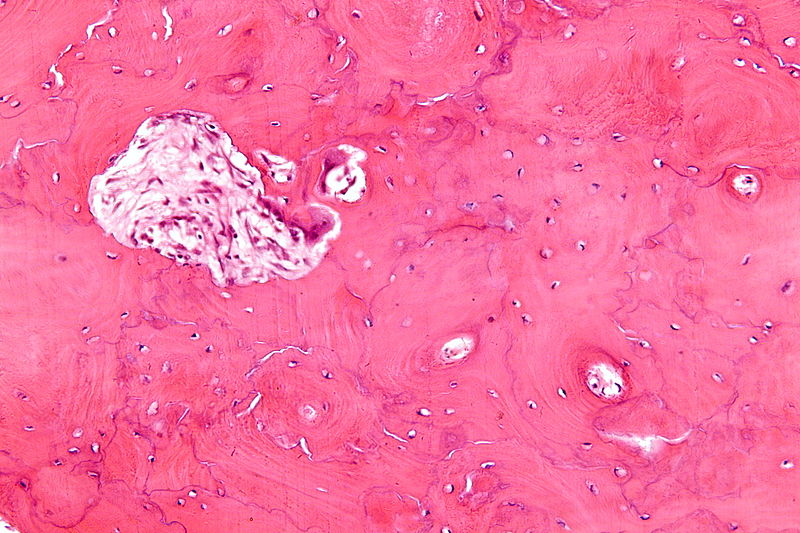

Histology of Paget disease of the bone reveals a mosaic pattern of lamellar bone.

Giant cell tumor of the bone is composed of multinucleated giant cells and stromal cells that occur in young adults.

Giant cell tumor of the bone typically arises in the epiphysis of long bones, usually the distal femur or proximal tibia.

Radiology of giant cell tumor of the bone classically shows a “soap-bubble” appearance on x-ray.

Giant cell tumors of the bone are locally aggressive, and they may recur after surgical removal.